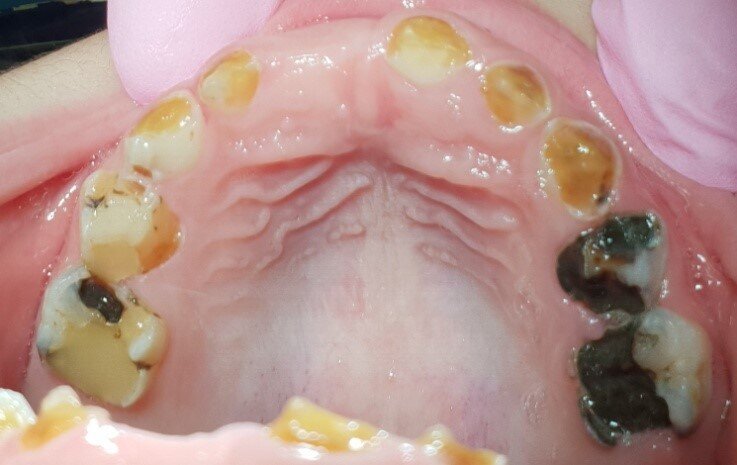

Afbeelding 4a: Kleurfoto’s op de leeftijd van 6 jaar, juli 2018. Alle cariëslaesies in de bovenkaak zijn arrested, in de 55, 64 en 65 met ondersteuning van SDF. Laesies die tijdens het aanbrengen arrested waren, zijn niet verkleurd.

Afbeelding 4b: Kleurfoto’s op de leeftijd van 6 jaar, juli 2018. Alle cariëslaesies in de bovenkaak zijn arrested, in de 55, 64 en 65 met ondersteuning van SDF. Laesies die tijdens het aanbrengen arrested waren, zijn niet verkleurd.

Jenny is 6 jaar. Er worden röntgenopnames en kleurenfoto’s gemaakt (Afb. 3 en 4). Op de röntgenfoto’s lijken de bovenmolaren ernstig aangetast, maar ze zijn hard en inactief. De niet-gerestaureerde bovenmolaren en kronen met gerestaureerde ondermolaren zijn vrij van ontsteking. Jenny kwam voor mondonderzoek om de 4-6 mnd.